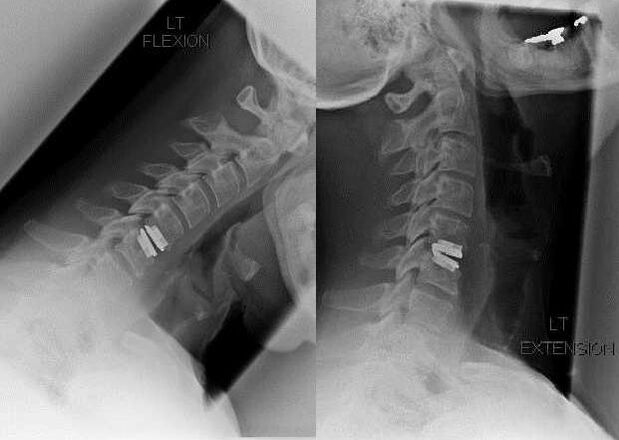

surgical intervention

Indications for surgical intervention include ineffectiveness of conservative treatment, as well as complications of cervical osteochondrosis, for example, discogenic myelopathy, vertebral artery syndrome, and radicular syndrome.The following operations are performed to decompress the spinal cord, blood vessels and spinal roots:

During the operation, it is possible to excision of bone fragments and ligaments and complete or partial removal of intervertebral discs.For small herniated disc herniations, laser ablation of the disc nucleus is often performed.

After excision of the spinal structures, stabilization of the motion segments of the spine is often required with spinal fusion or bone and skin autografts.